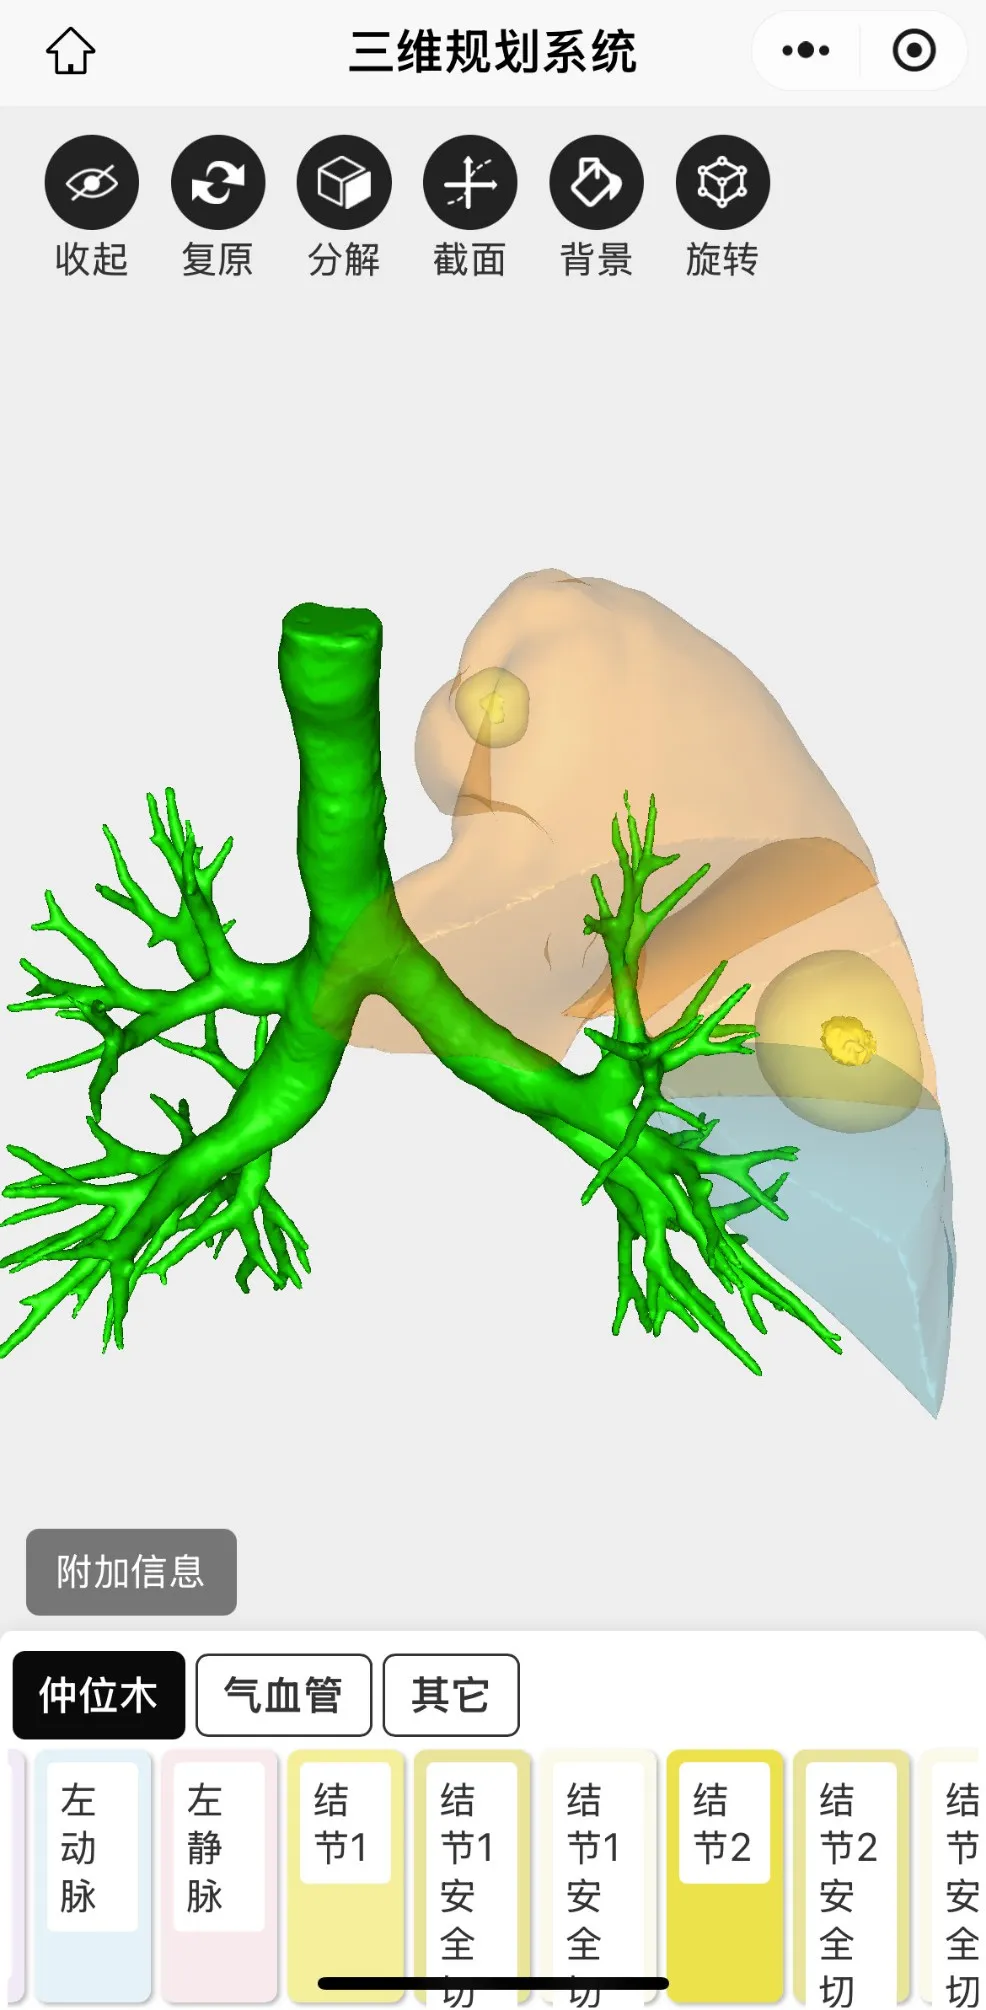

三維重建後圖片如下

最終為患者行左肺上葉S1+2c與S4a聯合亞段切除及S1+2a段(duàn)楔形切除術。患者術後2天出院,恢(huī)複良好,手術後對肺功能無影(yǐng)響。結節1病理為(wéi)原位癌,結(jié)節2為良好病灶。患者對91麻豆视频(men)手術方(fāng)案非(fēi)常滿意,痊(quán)愈出院。

三維重建輔助下肺癌精準肺段切除術,是一種先進的肺癌手術方式。主要(yào)借助CT影(yǐng)像數據,利(lì)用計(jì)算機技術對肺部、血管及支氣管等進行三維(wéi)立(lì)體建模,清晰呈現肺部解剖結構。優勢在於,醫生能精準定位腫瘤位置和(hé)邊界,規劃手(shǒu)術路徑,準確切除包含腫瘤的肺段,保留更多健康肺組織(zhī),提升患者(zhě)術後(hòu)肺功能和生活質量。同時減少術中出血(xuè)、降低損傷周圍組織風險。